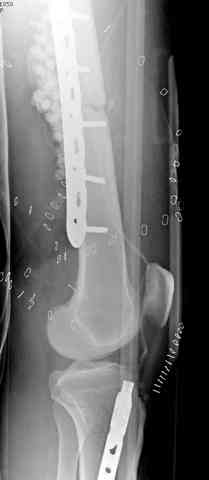

здесь случай с политравмой, перелом зафиксирован наружным фиксатором, после третьей irrigation&debridment фиксация бедра пластиной с последующей кожной пластикой.